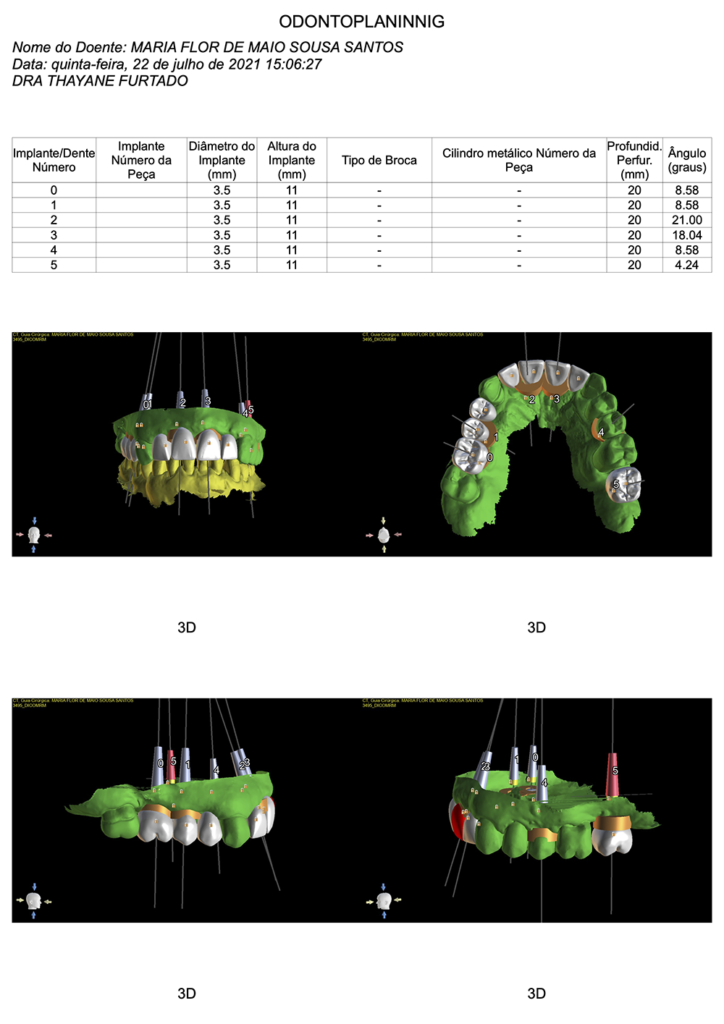

Através do escaneamento intraoral, foi realizado o planejamento das cirurgias guiadas (ODONTOPLANNING-BRASIL).

Impressão dos guias cirúrgicos superior e inferior.

Guia cirúrgico superior posicionado em boca antes das extrações dentárias.

Instalação dos implantes com o guia cirúrgico em posição.

Momento logo após a confecção dos implantes guiados superiores.